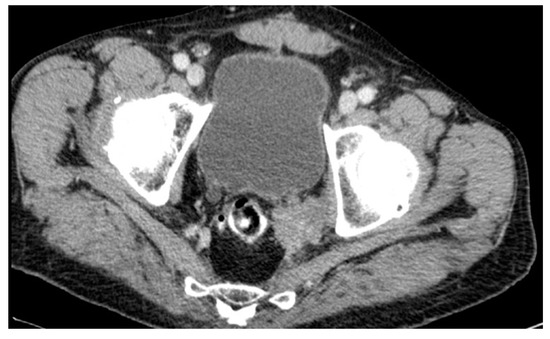

| 75 years | Female | ypT3ypN2a | 21 months | Anterior compartment |

| 68 years | Female | ypT2ypN0 | 108 months | Anterior compartment |